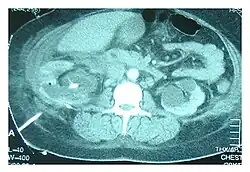

Tomografia computadorizada mostrando o tubo de nefrostomia, indicada pela linha branca no canto inferior esquerdo, em um caso de urinotórax em tratamento

Ultrassonografia abdominal e tomografia computadorizada podem ajudar a diagnosticar a condição subjacente do trato geniturinário. Se outros métodos forem inconclusivos, um diagnóstico preciso pode ser feito por uma cintilografia renal com tecnécio-99m, que mostra albumina marcada com 99Tc que se transloca para o espaço pleural a partir do trato geniturinário.[3]